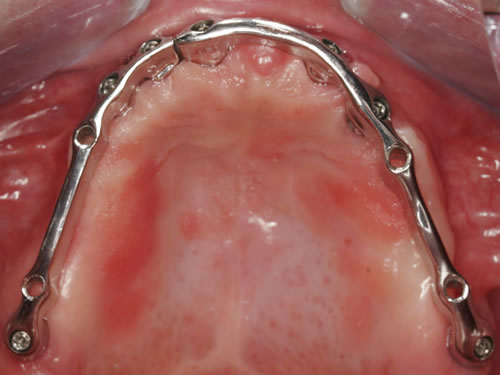

Für den zahnlosen Ober- und Unterkiefer werden dies häufiger Stegkonstruktionen oder Teleskopversorgungen sein (Abb. 8.8 bis 8.16).

Abb. 8.8: Individueller Steg auf 4 Implantaten im zahnlosen Unterkiefer.